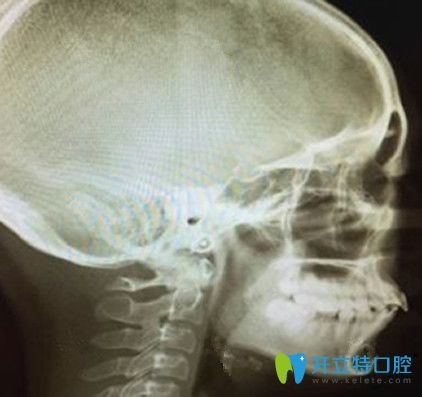

牙齒矯正術前拍片側面牙齒照片:

牙齒矯正術前拍片側面牙齒照片

首先,正畸的開始需要拍兩張x光片,確定牙齒問題是齒性還是骨性,或者是有沒有什么其他的肉眼無法解決的問題。

從這張側面的X光片看我不僅突嘴,而且似乎還少了一顆牙,嗚嗚嗚……真心想哭。